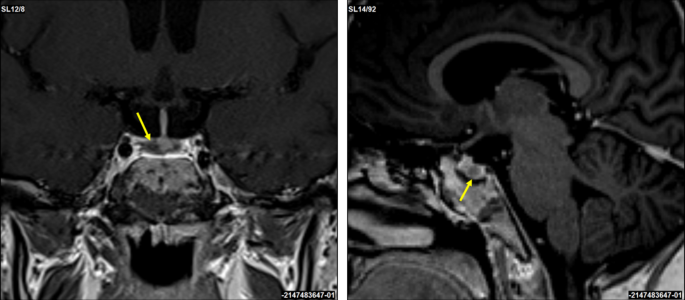

An increased neutrophil count and decreased eosinophil count were observed, although the white blood cell count was within the normal range (Table 1). Biochemical analysis showed that the serum potassium level was decreased (2.3 mEq/L). The serum total protein, albumin, blood urea nitrogen, and cholinesterase levels were mildly decreased. Renal function, hepatic function, and lipid profiles were within normal limits, except for elevated triglyceride levels. A spot urine test indicated an elevated urine protein-to-creatinine ratio (0.436 g/gCr) (Table 2). Regarding diabetes-related tests, fasting plasma glucose (91 mg/dL), glycated hemoglobin (HbA1c) (5.4%), and glycated albumin (GA) (12.9%) were all within their normal ranges. The serum C-peptide level was elevated. A 75 g oral glucose tolerance test (OGTT) conducted at 25+4 weeks of gestation showed serum glucose levels of 191 mg/dL at one hour and 212 mg/dL at two hours (Table 2), indicating postprandial hyperglycemia. Endocrinological evaluation revealed elevated morning serum cortisol levels with loss of diurnal variation. This hypercortisolism is accompanied by suppressed plasma adrenocorticotropic hormone (ACTH) levels (Table 3). The 24-hour urinary free cortisol (UFC) level was markedly elevated (1,380 μg/day). In contrast, dehydroepiandrosterone sulfate (DHEA-S) levels decreased. Serum thyroid-stimulating hormone (TSH) was markedly decreased (0.091 IU/mL), accompanied by mild reductions in free T3 (1.65 pg/mL) and free T4 (0.65 ng/dL), which indicated central hypothyroidism. Abdominal ultrasonography revealed a nodule in the right adrenal gland with a maximum diameter of approximately 30 mm (28 × 27 × 25 mm) (Figure 2A). Abdominal magnetic resonance imaging (MRI) detected a 27-mm well-defined nodular lesion at the same location, which demonstrated a signal drop on opposed-phase images (Figure 2B). Obstetric ultrasonography revealed an estimated fetal body weight of 742 g (adequate for gestational age) (Figures 3A–3C), an amniotic fluid index of 16.4 cm (Figure 3D), and no major structural anomalies of the fetus. From the day of referral, oral nifedipine (40 mg/day) was initiated as antihypertensive therapy. Potassium chloride (KCl) was administered orally.

Figure 2: Radiological findings of the right adrenal tumor (white arrow)

(A) Trans-abdominal ultrasonography image and (B) coronal section of the trunk on MRI.